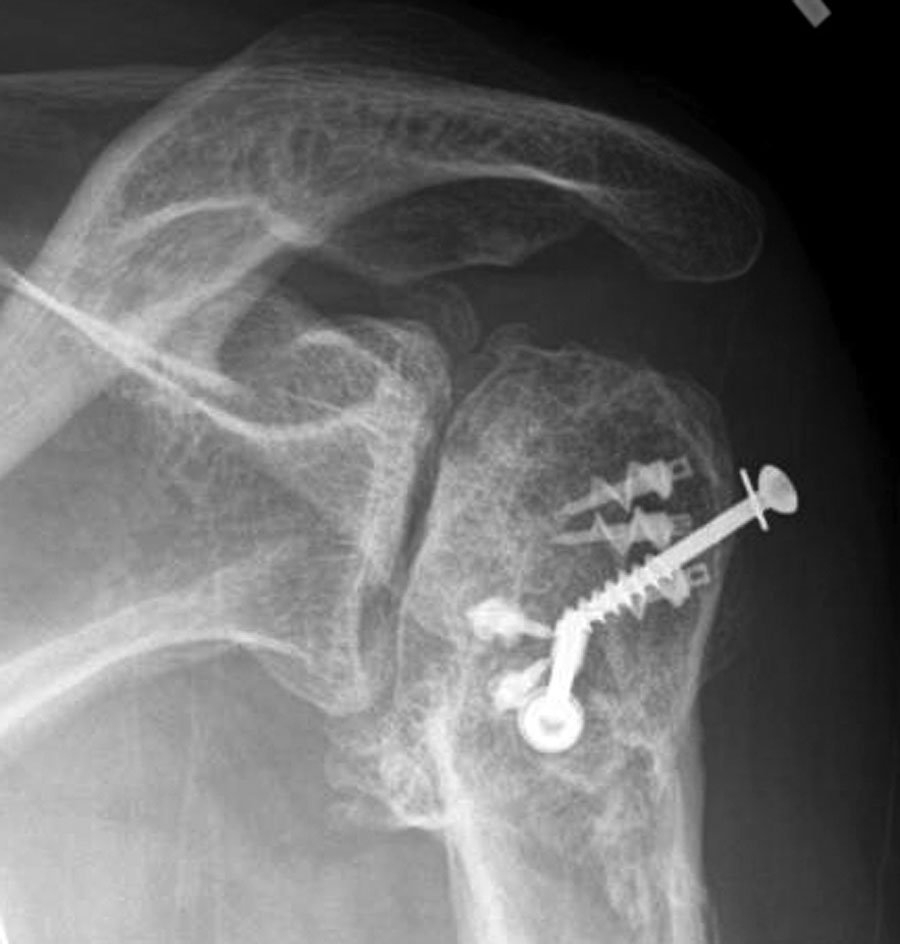

Here is an anteroposterior (AP) and an axillary view typical of shoulders with post traumatic arthritis.

The upper view, the AP shows collapse of the humeral head, osteophyte formation, sclerosis, screws and suture anchors.